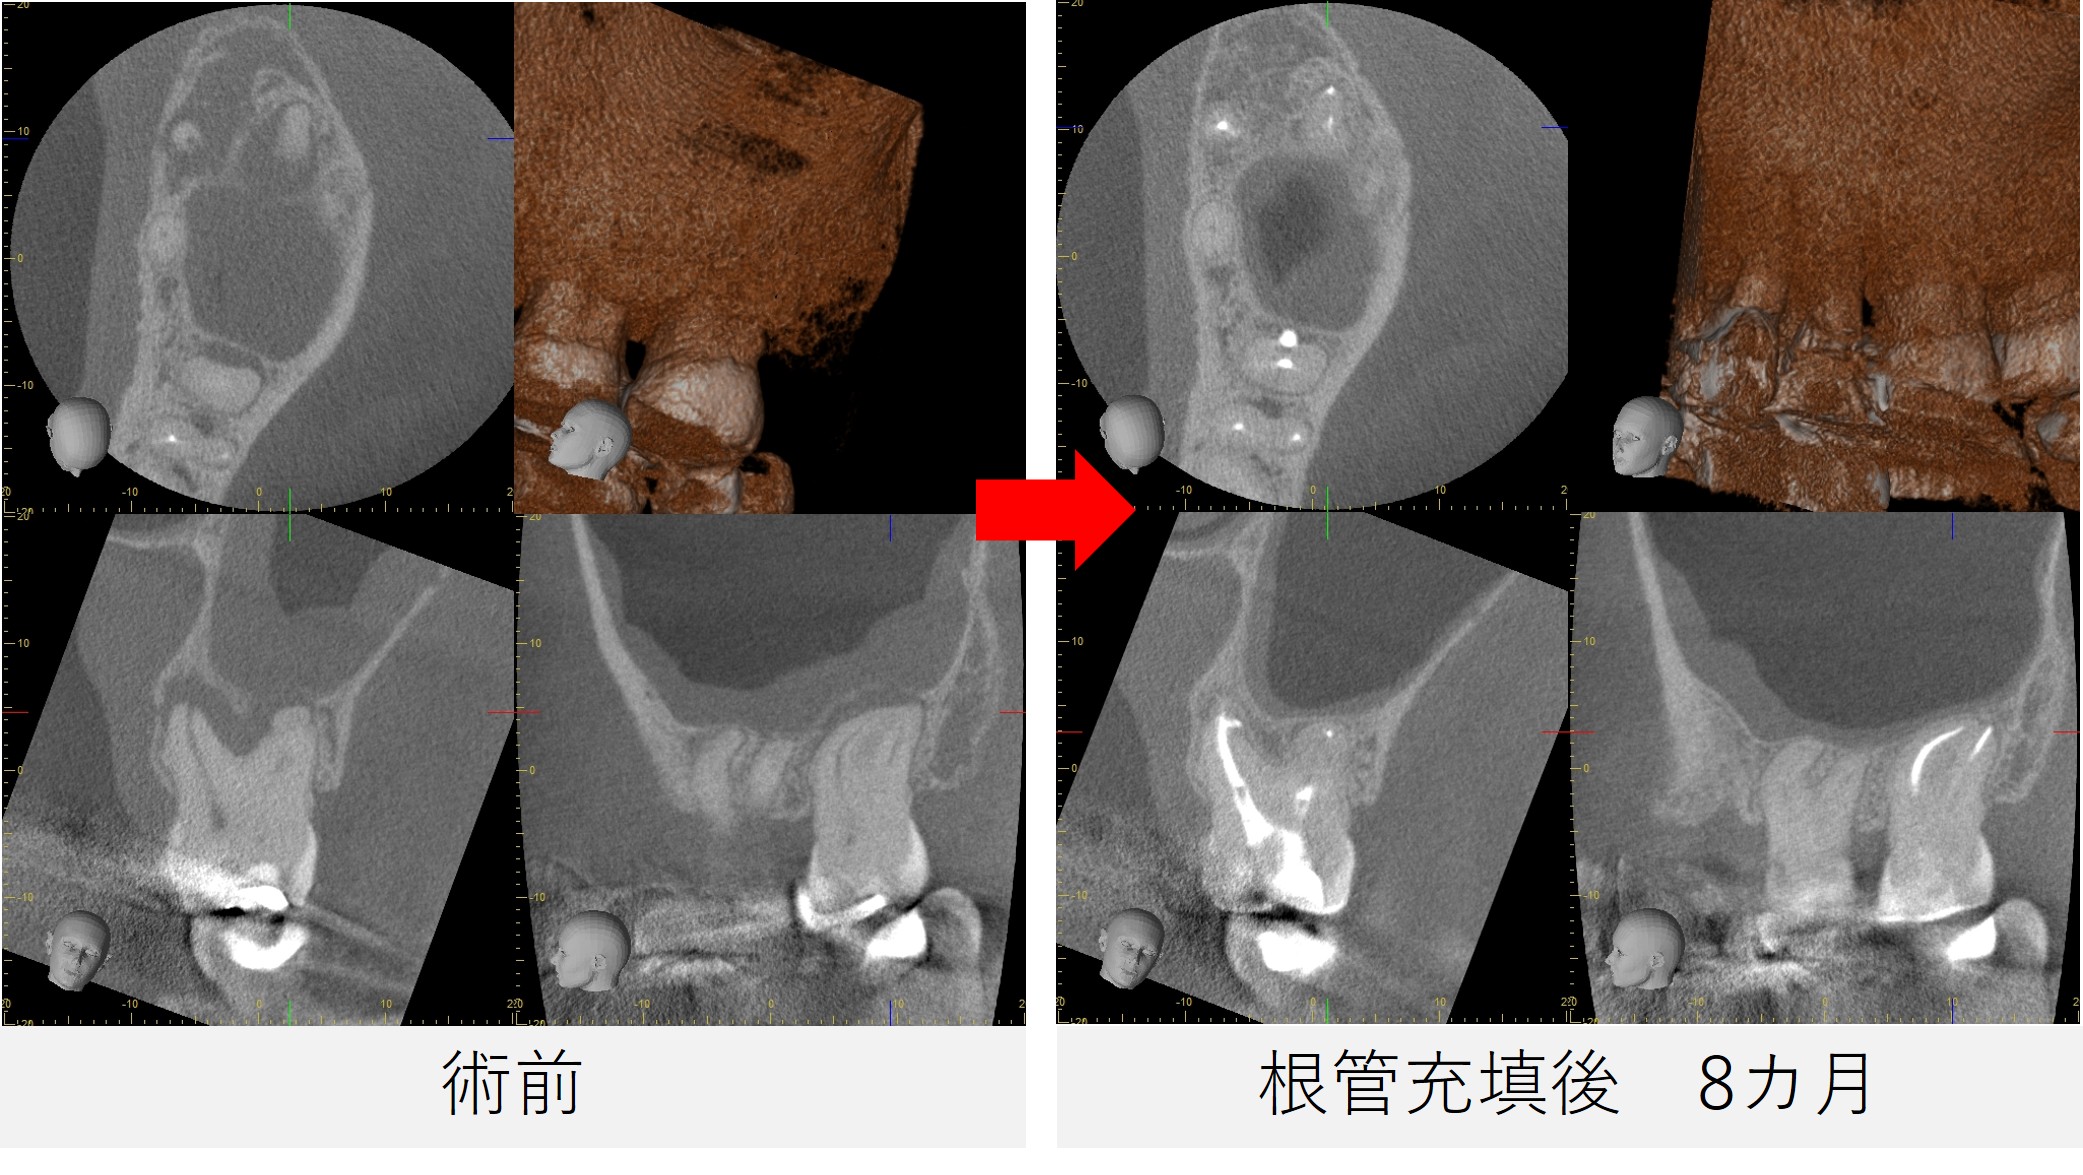

●レントゲン・CT画像所見

レントゲンおよびCT画像では、左上7番の根尖部に黒い影(骨のない部分)を認め、炎症が上顎洞(鼻と繋がっている空洞)にまで及んでいる所見が確認されました。

また、根管は強く湾曲しており、治療の難易度が高い症例でした。

根管充填後から8カ月

- 痛みはなく、鼻の症状も認められませんでした。

- レントゲンおよびCT撮影を行い、根尖部の黒い影が縮小し、骨の回復傾向が確認されました。

- 炎症の改善が見られたため、最終補綴(被せ物の作製)へ移行する予定としました。